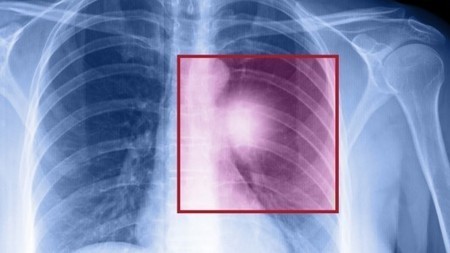

Information contained in the two-page guide includes lung cancer statistics, The recommendation for the use of chest X-ray as the mandatory first-line investigation for lung cancer is based on the New Zealand Guideline Group PowerPoint Presentation ... Fetch This Document